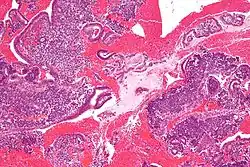

In histopathology, a small-blue-round-cell tumour (abbreviated SBRCT), also known as a small-round-blue-cell tumor (SRBCT) or a small-round-cell tumour (SRCT), is any one of a group of malignant neoplasms that have a characteristic appearance under the microscope, i.e. consisting of small round cells that stain blue on routine H&E stained sections.

These tumors are seen more often in children than in adults. They typically represent undifferentiated cells. The predominance of blue staining is because the cells consist predominantly of nucleus, thus they have scant cytoplasm.[1][2]